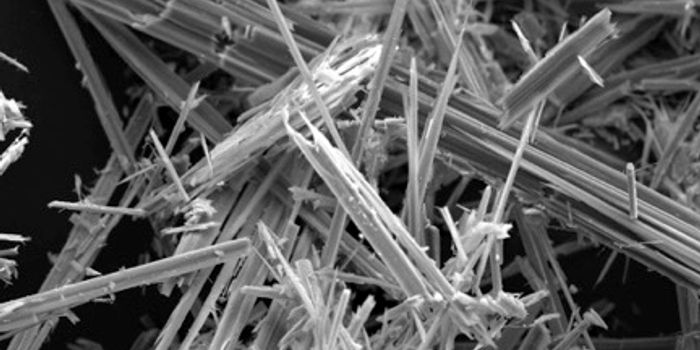

MAR 23, 2016Clinical & Molecular DXMany people have heard of mesotheliomas through frightening television commercials. But little is known about treatment ...